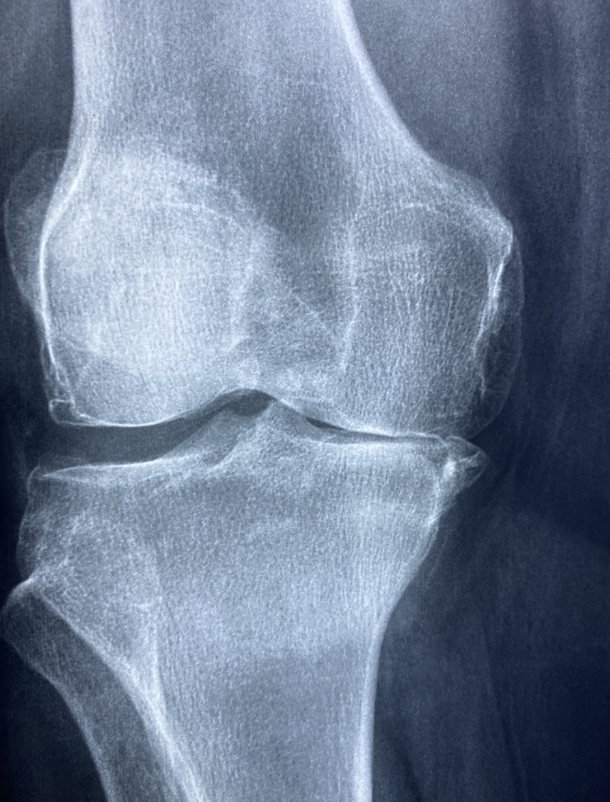

퇴행성 관절염은 나이가 들면서 관절의 연골이 점점 닳아 없어지는 질환이에요. 연골이 손상되면 뼈끼리 직접 마찰하게 되어 통증이 발생하고, 무릎이 뻣뻣해지면서 움직이기 어려워질 수 있어요. 하지만 올바른 생활 습관과 꾸준한 관리를 통해 퇴행성 관절염을 예방하고 진행 속도를 늦출 수 있습니다. 오늘은 퇴행성 관절염을 예방하고 관리하는 방법에 대해 알아볼게요! 😊